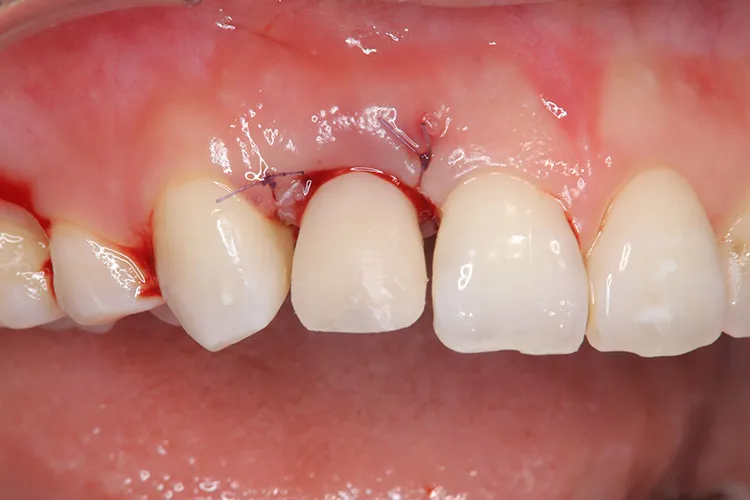

前歯1本

- 治療期間

- 3ヶ月

- 費用

- 51万円(税込)

治療前

治療後

レントゲン画像

治療内容

怪我で歯が折れてしまったケースです。前歯なので抜歯即時埋入で対応しました。即時で仮歯まで入れ、見た目の回復を行いました。その後歯肉が治りインプラントが安定したタイミングで最終の被せ物を装着しオペから3ヶ月で治療完了しました。